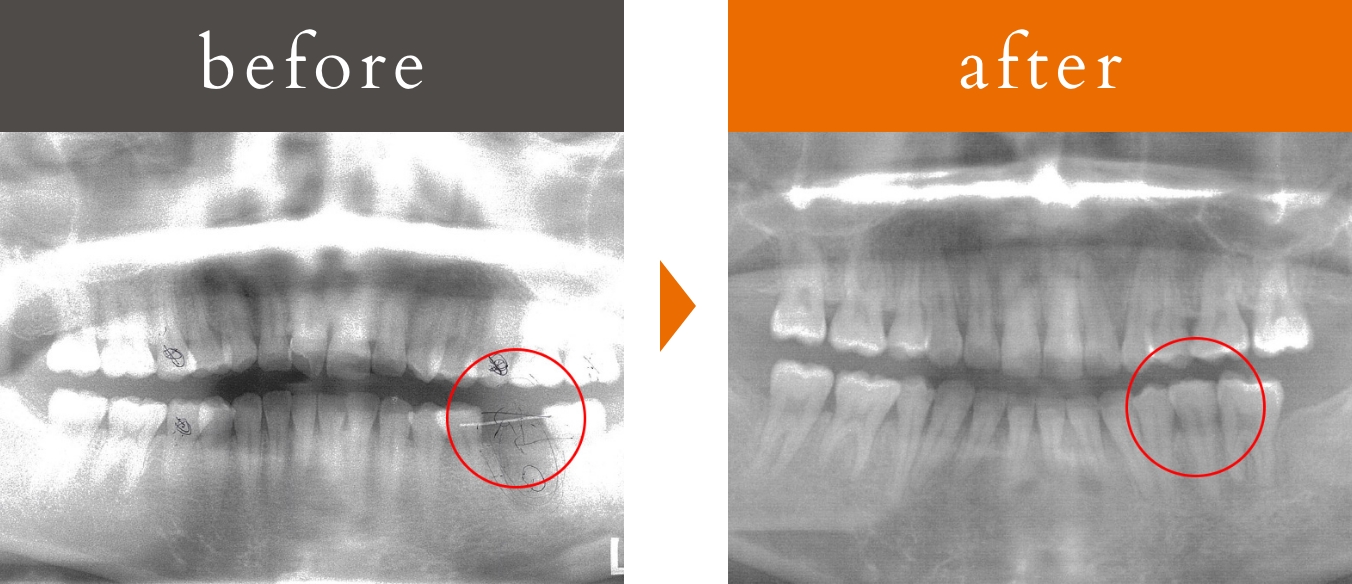

第一大臼歯の欠損

治療概要

主訴:下顎第一大臼歯の欠損による噛み合わせの不安定さ

治療内容:3D-LST矯正治療法を用い、抜歯を最小限に抑えながら歯の近心移動を実施。咬合・顔のプロフィールも改善。

患者年代・治療期間

20代女性・3年8ヶ月(難治症例)